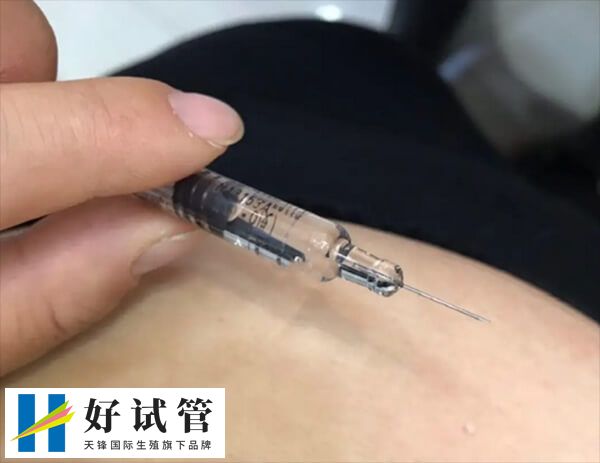

试管临床上,长方案促排卵泡治疗周期应用的比较多,不过因个体之间存在较大的差异,所以部分患者在使用长方案促排卵之后,可能会出现卵泡大小不一样的情况,而这也可能是以下几点导致的。

患者在长方案促排卵过程中,若是个体对药物的反应不同,或是有错误用药的情况下,那么也可能会导致卵泡发育速度不一致,对此建议患者应该及时寻求医生的帮助。